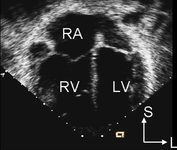

Imagen de ecocardiografía de 4 cámaras apical que demuestra agrandamiento ventricular derecho en un paciente con una comunicación interauricular (CIA). (AD) aurícula derecha; (VD) ventrículo derecho; (VI) ventrículo izquierdo

Imagen cortesía de Patrick W. O'Leary, MD